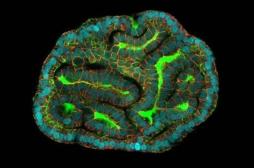

cellule souche